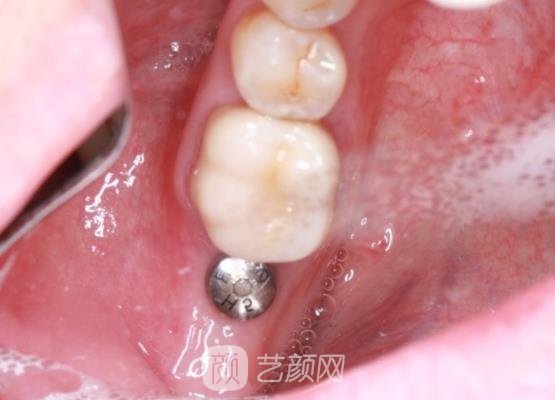

种植牙手术案例:

小时候我太顽皮了,造成了我的牙齿出现了缺失的问题,看起来一点也不美观,对我的外貌有着很大的影响,说话的时候我也不敢很大声,因为我的牙齿问题我也总是很困扰,所以我一直想要通过种植牙手术来进行改良。

确定好手术方案以后手术就开始了,可能是因为医生医美技术比较厉害的原因,所以手术过程中剧烈的疼痛感我也是没有感觉到的,手术也是比较方便的,几个小时就结束了,没有浪费我很多的时间,这是我没有想到的。

刚结束手术时,我的牙龈处还有一些肿胀的情况,医生告诉我这些现象比较正常,然后给我开了一些消炎药让我定时服用,果然吃了消炎药以后,我牙龈的肿胀情况缓解了很多。

几个月以后,我的牙齿已经恢复好了,口腔也没有一些异物的感觉,果然手术是很有成果的,医生的服务态度良好,手术技术也是比较厉害的,以后如果有朋友需要做这项手术的话,我也一定会推荐这家医院的。